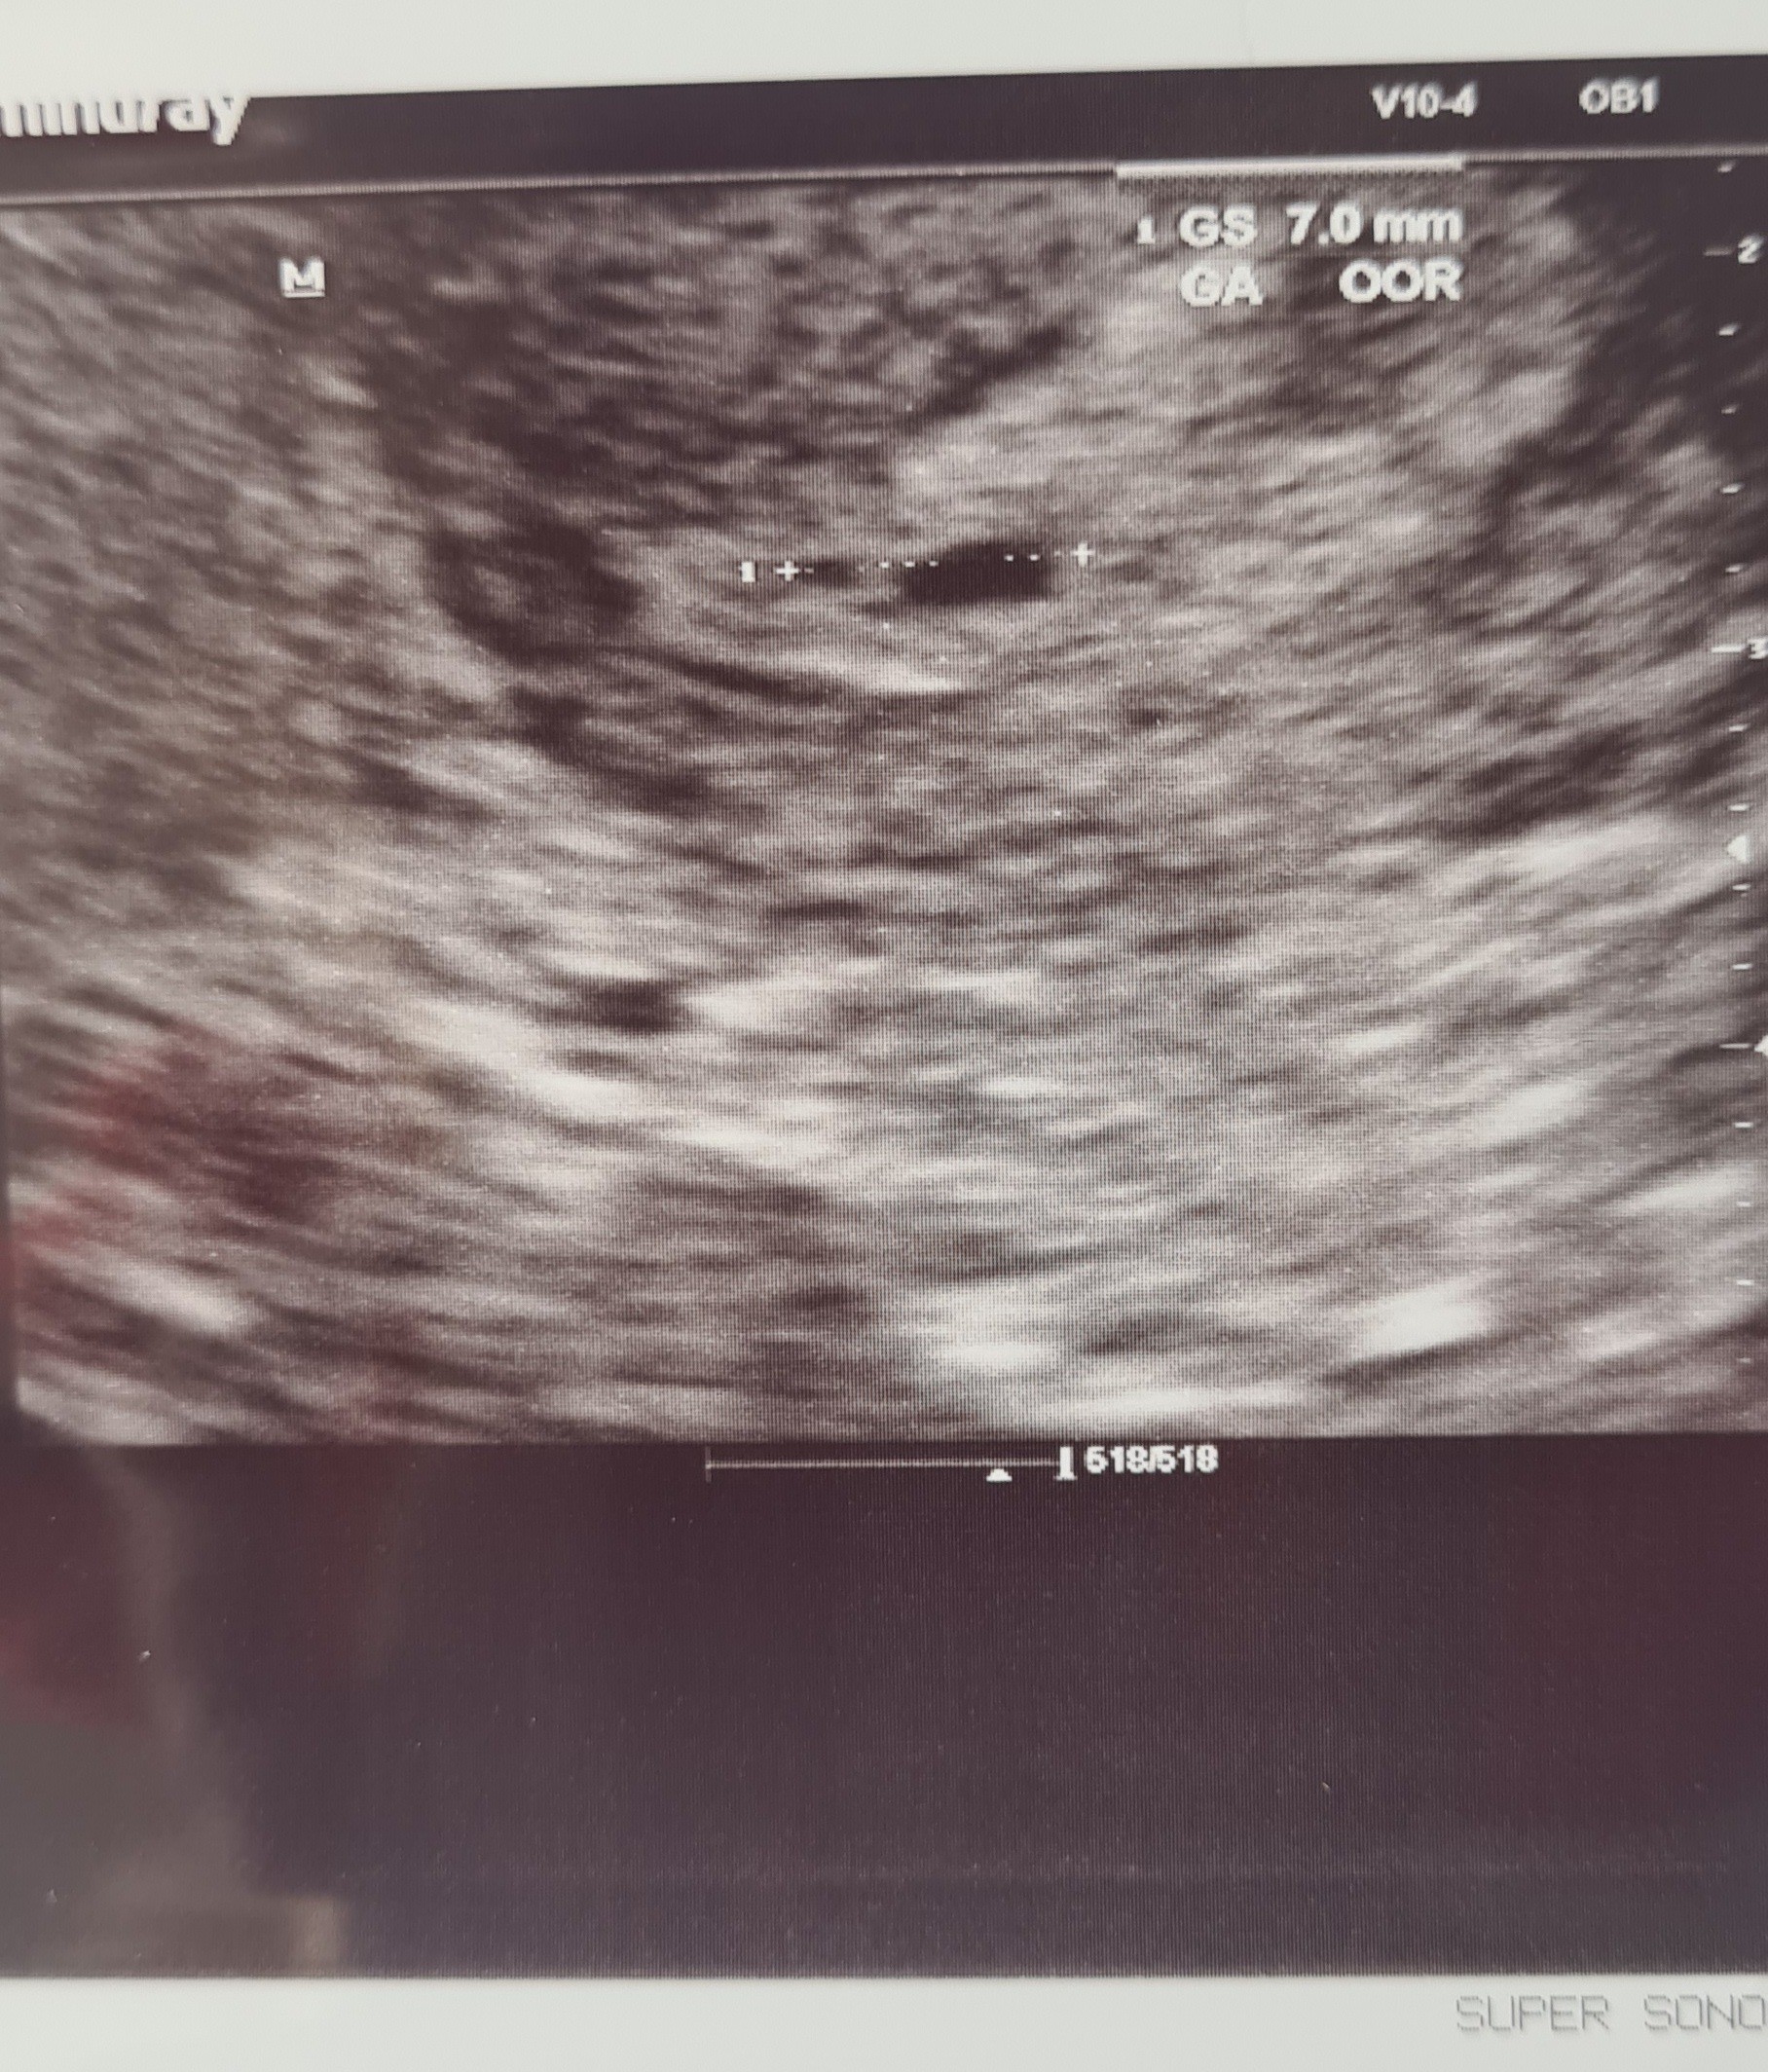

Na USG mam napisane 6+0

Doktor powiedział, że zarodka poniżej 2 mm aparat nie wyłapie. Powiedział że albo jest jeszcze za mały albo już go nie ma.

U mnie to pierwsza ciąża, więc jest to nieco stresujące. Usg poniżej, co o tym myślisz?

U mnie to pierwsza ciąża, więc jest to nieco stresujące. Usg poniżej, co o tym myślisz?Zobacz załącznik 1306390

No pęcherzyk ciążowy jest, więc trzeba być dobrej myśli. Planujesz na betę iść tylko raz w czwartek?